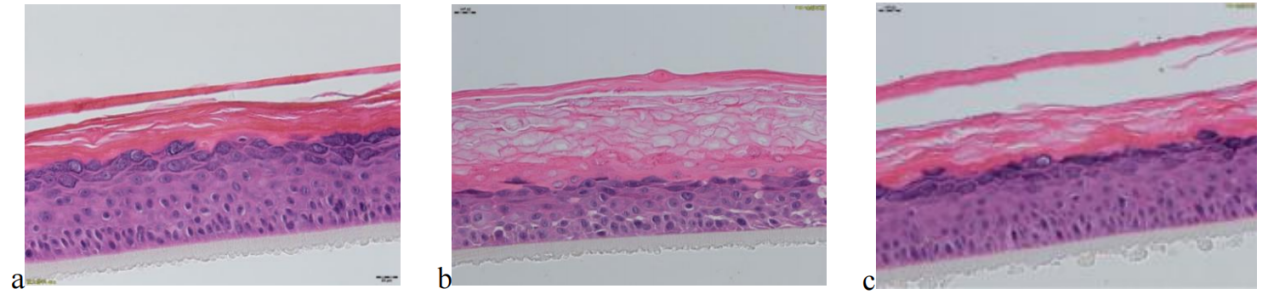

待測活性物與BAP聯合作用于EpiKutis® 皮膚模型后,形態學結果見圖6。與空白對照組(Control)相比,刺激組(BAP)的角質層增厚、排列疏松、空泡明顯且分化不完全;活細胞層(顆粒層、棘層、基底層)活細胞數目減少,基底層細胞空泡明顯,排列疏散。

圖 6 不同處理條件下表皮模型的形態學變化情況(放大40倍)

(a.空白對照組,b.BAP刺激組,c.待測活性物組)